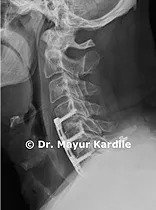

Case Example: ACDF for Cervical Radiculopathy

A 51-year-old man presented with pain and weakness in his right arm. MRI revealed foraminal narrowing and nerve root compression at C4-5, C5-6, and C6-7 levels. Dr. Kardile performed ACDF surgery through a small transverse incision over the front of the neck: • Disc removal and nerve decompression at C4-5, C5-6, C6-7 • Cage insertion and plate fixation • Patient regained full strength in right arm over 6 months post-surgery • Excellent long-term outcome

Case Images